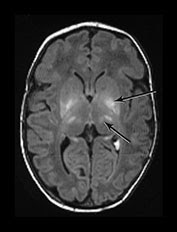

| Ausência do hipersinal em globo pálido esperado e presença de hipersinais em tálamo e gânglios da base. |

| Alterações em núcleo ventro-lateral do tálamo e Putâmen |

- A asfixia aguda grave está associada a lesões nos gânglios basais, tálamo, tronco encefálico, hipocampo e tratos corticoespinhais em torno da fissura central. Isso foi denominado envolvimento cortico-subcortical central. Este é o padrão mais comum de lesões após a angústia fetal aguda durante as contrações e o parto.